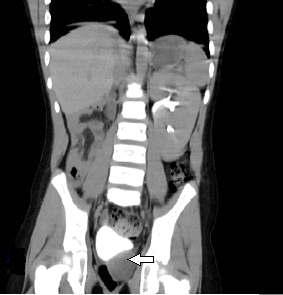

Se le realiza ecografía en la que se observó en proyección de hipogastrio imagen ecolúcida, redondeada, de paredes bien definidas, regulares de 32 x 29 mm en contacto con la pared posterior hacia el lado izquierdo que impresiona quiste de vesícula seminal. La tomografía axial computarizada demostró la ausencia de la unidad renal derecha por nefrectomía anterior, se evidencia imagen hipodensa, de paredes bien definidas, redondeada hacia la pared posterior izquierda de la vejiga (Figura 1) que no realza con el uso del contraste, en relación a quiste a nivel de la vesícula seminal izquierda que oscila entre 5-13UH (Figura 2 y 3). Se decidió como conducta terapéutica punción y drenaje por aspiración de la lesión. Se mantiene en seguimiento, hasta la fecha no se evidencia recidiva.

Fig. 1. Tomografía computarizada simple corte axial donde se evidencia la imagen hipodensa de aspecto quística en la cara posterior de la vejiga hacia su lado izquierdo.

Fig. 3. Tomografía contrastada corte sagital donde se observa la imagen antes descrita en cara posterior de la vejiga.